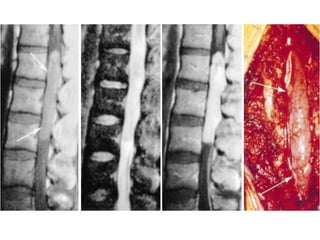

ESPONDILODISCITE